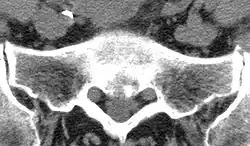

(1) (Rand-)Osteophyt

(2) subchondrale Sklerosierung

(3) Geröllzyste

(4) Gelenkspaltverschmälerung

Der Patient berichtet bei der Anamnese über Gelenkschmerzen, anschließend muss geklärt werden, bei welchen Gelegenheiten dieser Schmerz auftritt. Es folgt die klinische Untersuchung der Gelenkkontur, der Funktion, der Bandstabilität, der umgebenden Muskulatur. Dann schließt sich, je nach Erfordernis, eine bildgebende Diagnostik an, wie beispielsweise Röntgen, Computertomographie (CT) oder Magnetresonanztomographie (MRT). Zeichen einer bestehenden Arthrose sind dabei eine Verschmälerung des Gelenkspaltes, Sklerose (eine reaktive Knochenverdichtung zu beiden Seiten des Gelenkspaltes), Osteophytenbildung an den Gelenkrändern und subchondrale Zystenbildungen des gelenkbildenden Knochens, die durch feine Rissbildungen des Knorpels und Durchtritt von Gelenkflüssigkeit in die darunter liegende Knochenschicht entstehen. Eine Verschmälerung des Gelenkspalts deutet dabei auf eine Arthritis oder eine Arthrose hin, je nachdem, ob der gelenknahe Knochen verdünnt oder verdickt ist.[17]